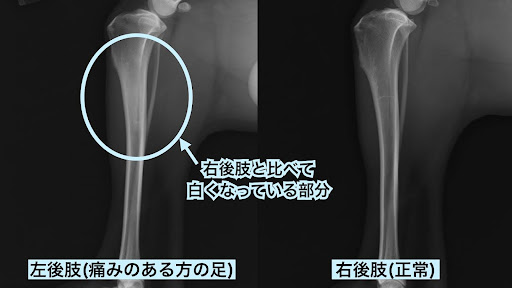

今回撮影したレントゲン写真をご覧ください。

痛みの反応のあった左後肢の脛骨の中央部分が、正常な右後肢に比べて白くなっているのが分かりますね。

このレントゲン画像と症例の年齢などの情報から、汎骨炎が強く疑われました。